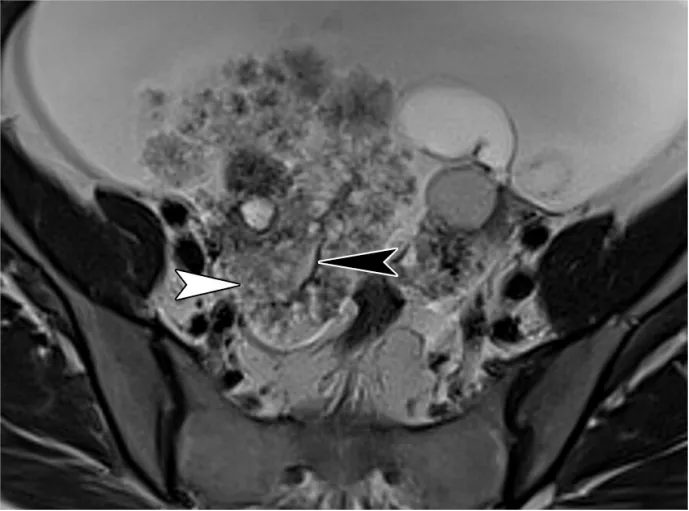

对于子宫旁/卵巢旁来源的病变,深部子宫内膜异位症是首要考虑的疾病(10)。深部子宫内膜异位症是一种严重的类型,表现为具有腹膜下延伸的纤维化病变。它通常为多灶性,主要累及盆腔,特别是附着于子宫 torus 的宫骶韧带。其他常见的受累部位包括直肠乙状结肠(“蘑菇帽”征)、子宫直肠陷凹、阴道、圆韧带、膀胱和卵巢表面。在晚期病例中,卵巢可能移位至子宫后方,形成“卵巢接吻”征(图27)。深部子宫内膜异位症在T2加权成像和弥散加权成像上表现为低信号增厚区、光滑或毛刺状结节,以及可能牵拉邻近结构并导致结构变形的浸润(例如子宫后屈、子宫偏斜、“卵巢接吻”征和肠管成角)。由于异位子宫内膜腺体中存在血液,深部子宫内膜异位症在T2加权成像和脂肪抑制T1加权成像上偶尔可能出现高信号灶。

图27. 一名46岁女性盆腔疼痛患者的双侧子宫内膜异位囊肿和深部盆腔子宫内膜异位症。轴位T2加权图像显示双侧子宫内膜异位囊肿(*)伴T2信号阴影。在子宫、卵巢和直肠乙状结肠之间可见由深部子宫内膜异位症引起的T2低信号瘢痕(箭头)。这种瘢痕会牵拉结肠,并将卵巢向后移位至子宫,即所谓的卵巢接吻征。